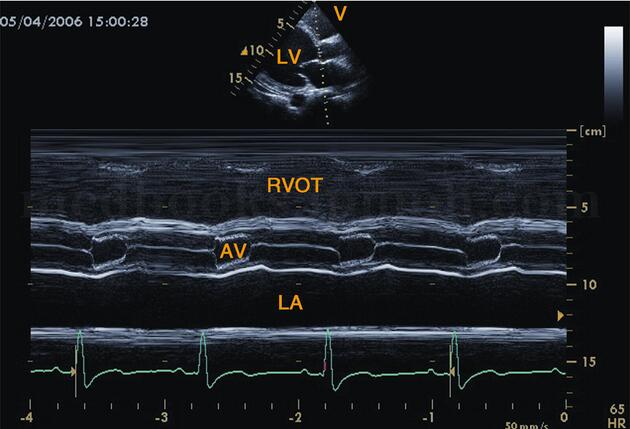

(3)心底波群见主动脉振幅减低或低平,主动脉瓣开放小,关闭速度减慢(图2‐1‐187)。

图2‐1‐187 心底波群M型超声主动脉根部振幅减低,瓣膜开放小,关闭速度减慢